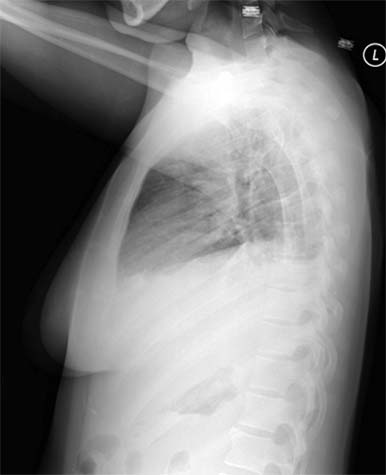

Lateral chest on someone with pneumonia. The pneumonia is the white substance in the lower part of each lung.

Note: Images are shown for illustrative purposes. Do not attempt to draw conclusions or make diagnoses by comparing these images to other medical images, particularly your own. Only qualified physicians should interpret images; the radiologist is the physician expert trained in medical imaging.